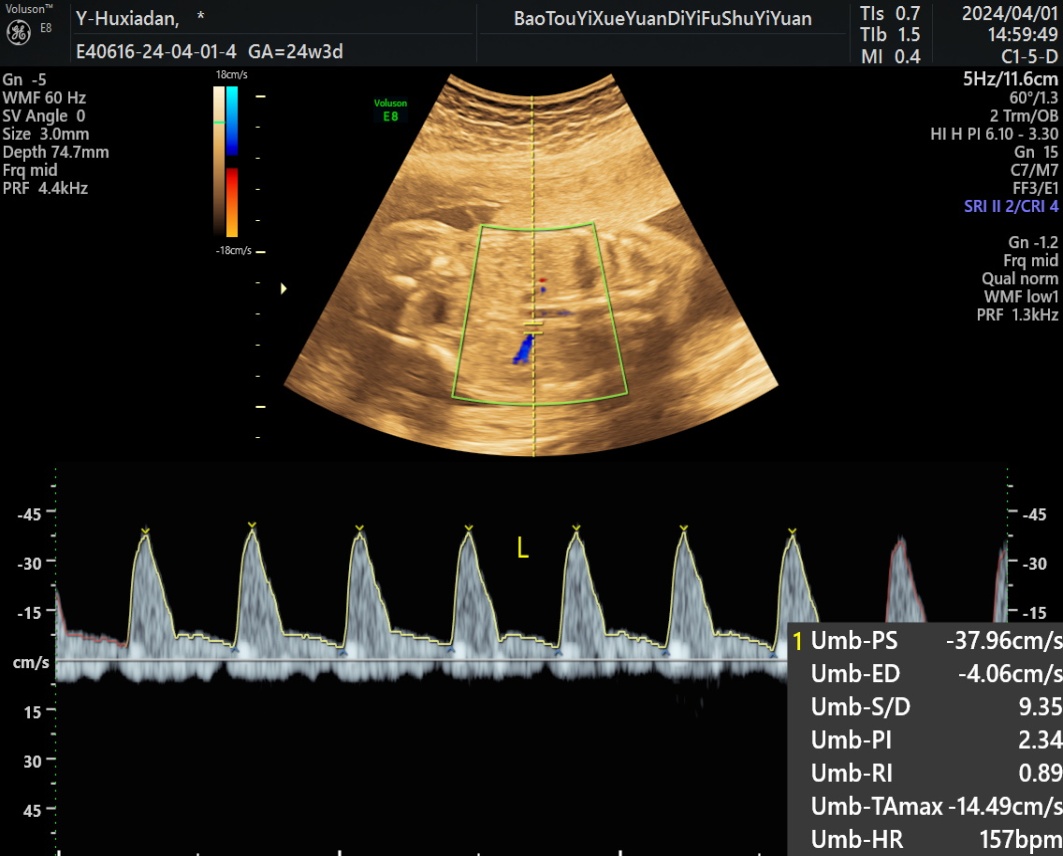

1) 200例胎儿UA、MCA、RA、UtA多普勒全部都被记录(图1图2)其中20~23周50胎,24~27周50胎,28~31周50胎,32~36周50胎,不同孕周血流参数测量值见表1~4

Figure 1. Left RA spectrum of a normal fetus at 24w3d of gestation

1. 孕24w3d正常胎儿左侧RA频谱图